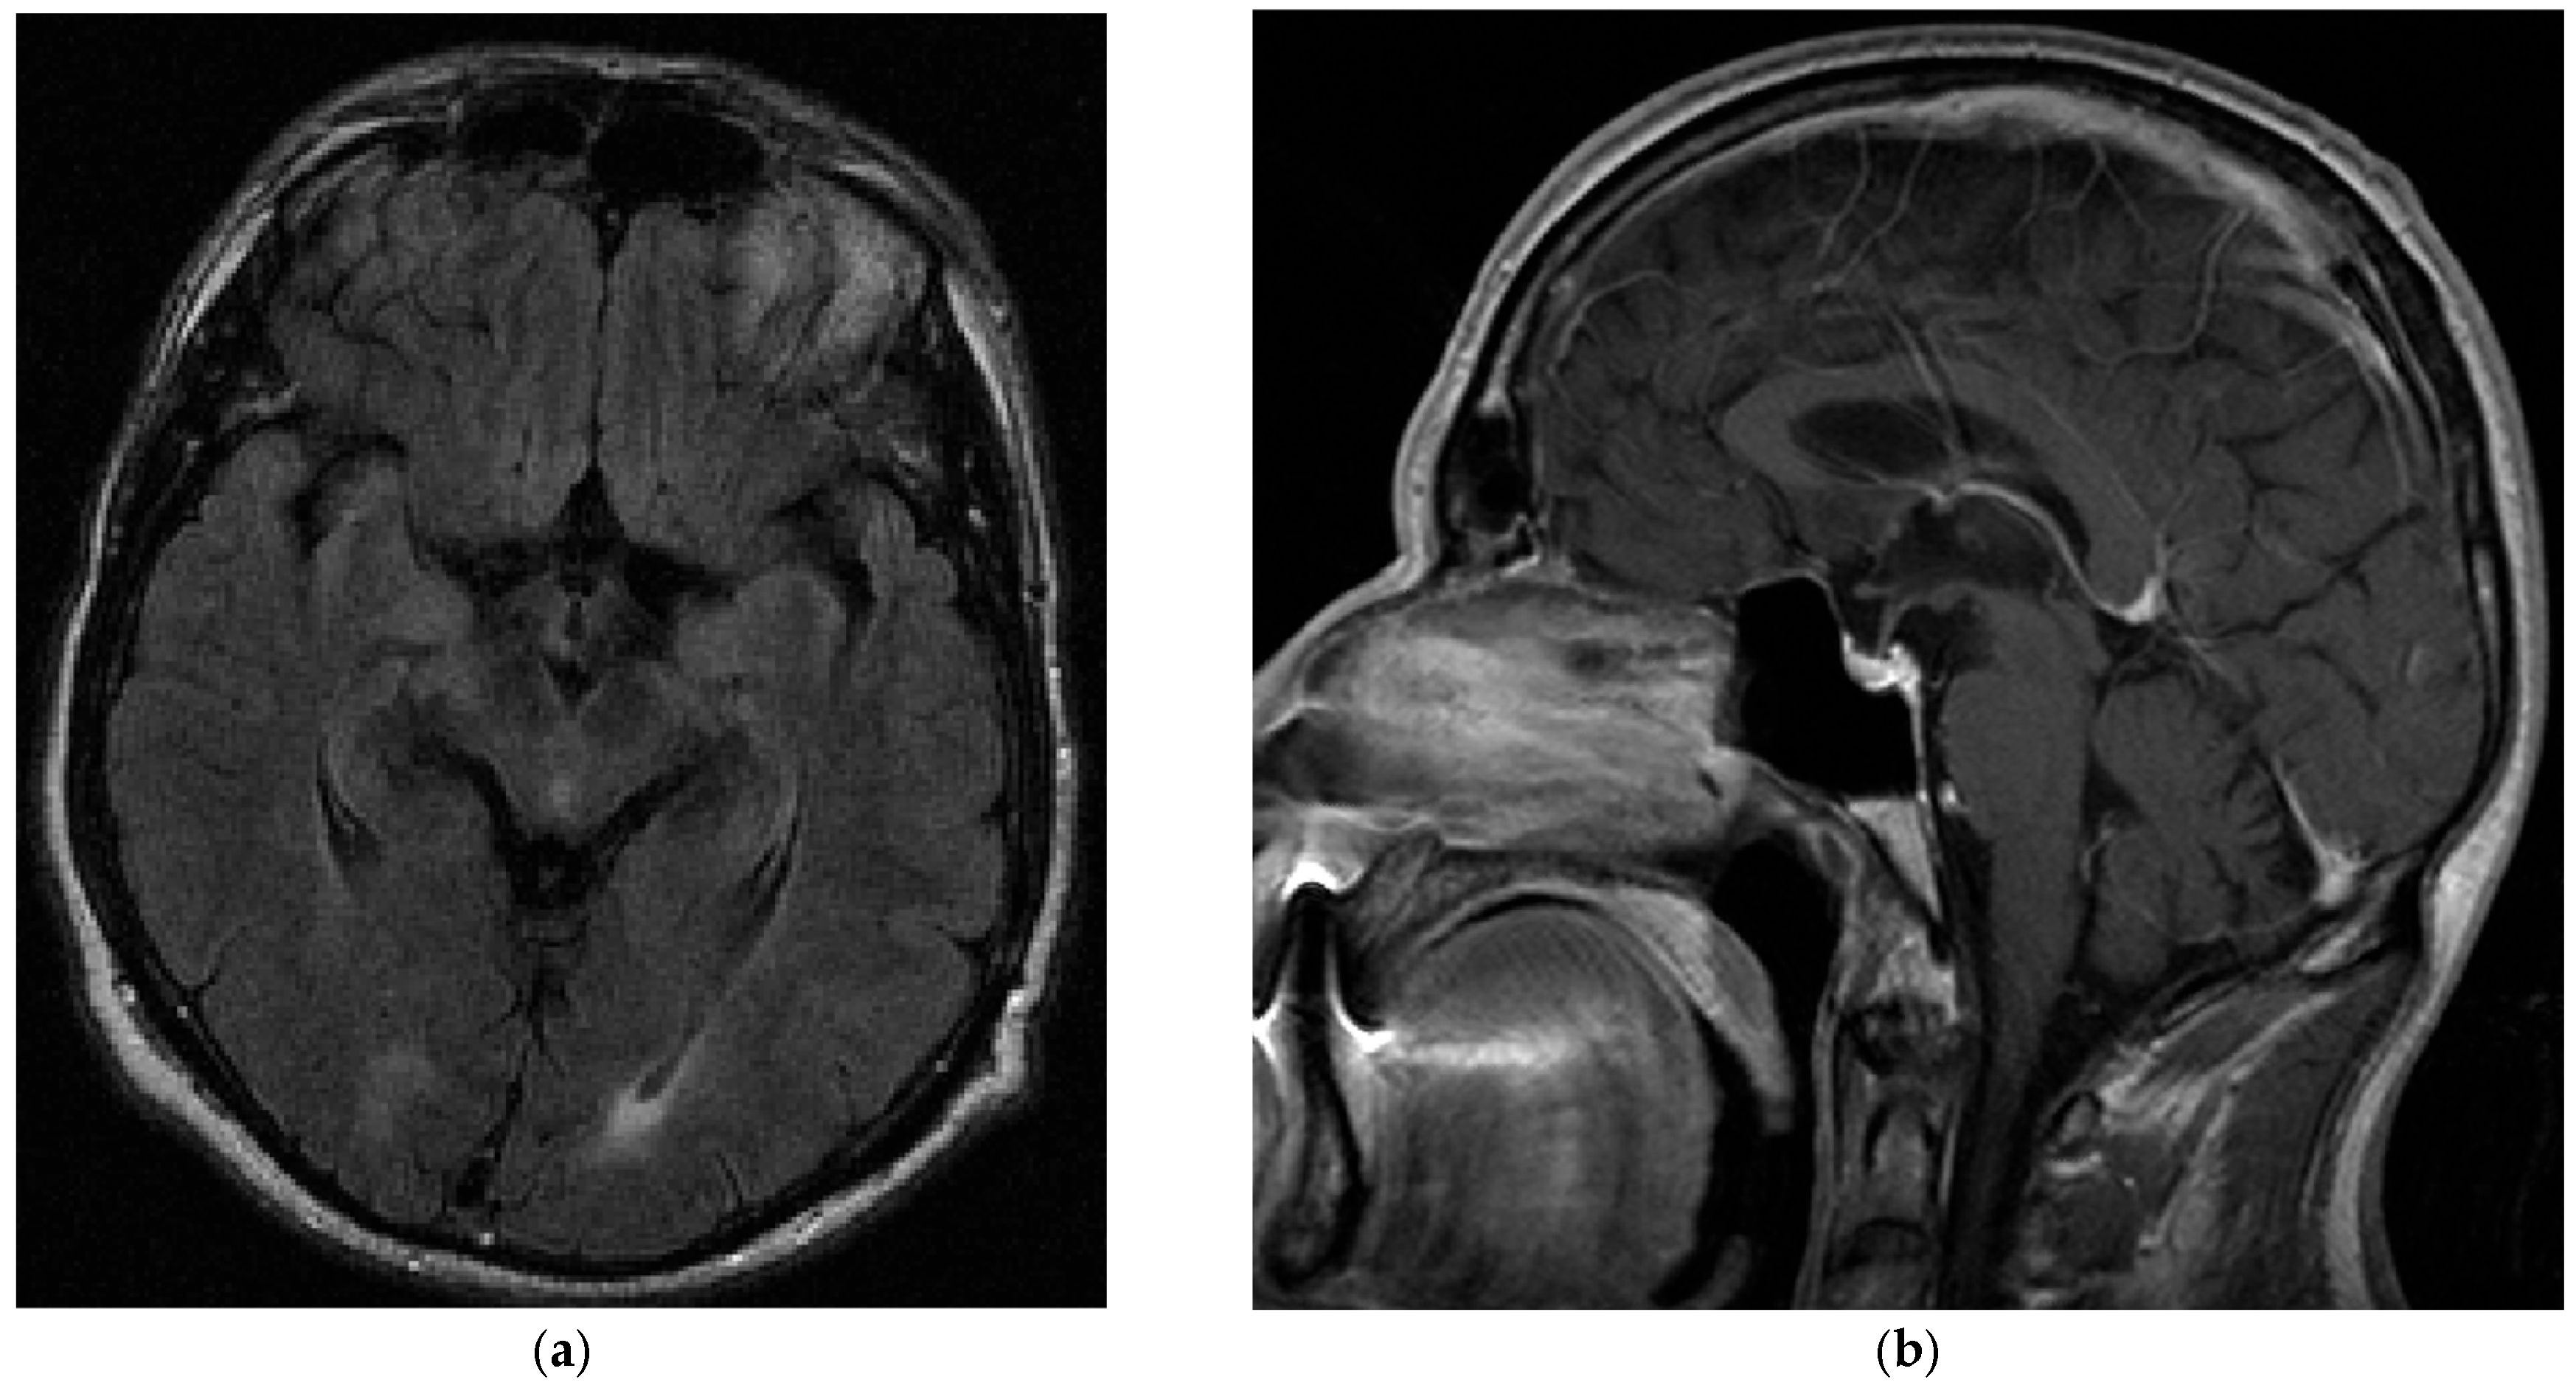

3. Case Report